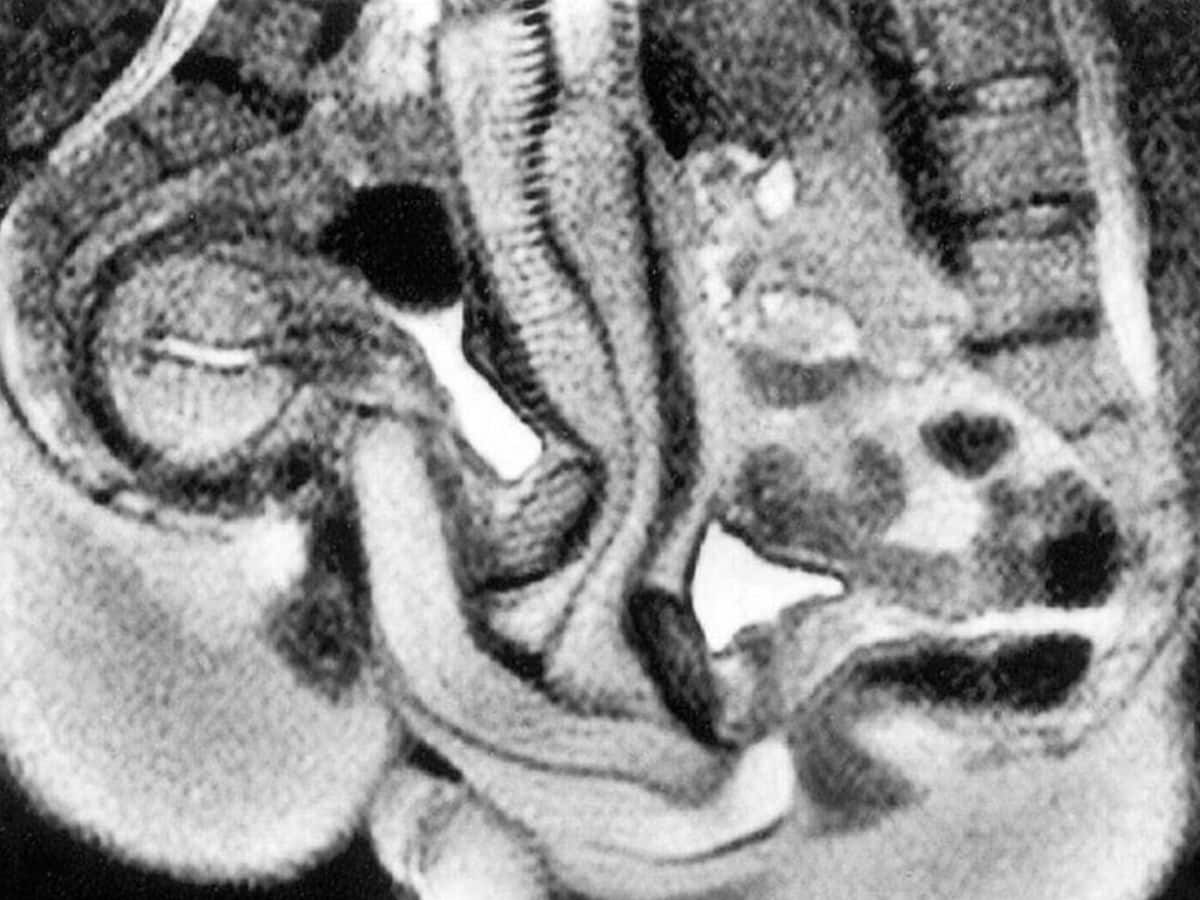

Σύμφωνα με τις μαγνητικές τομογραφίες από το πείραμα, κατά τη διάρκεια της σεξουαλικής επαφής, το ανδρικό μόριο δεν παραμένει ευθύ. Αντιθέτως, καμπυλώνεται προκειμένου να προσαρμόζεται στο σχήμα του γυναικείου κόλπου– σε αντίθεση με όσα υποστήριζαν παλαιότερες θεωρίες, που φτάνουν πίσω στην εποχή του Λεονάρντο ντα Βίντσι.

Η μελέτη διαπίστωσε ότι το πέ:ος λυγίζει σαν μπούμερανγκ κατά τη διάρκεια της πραξης.

Ο κόλ:πος δεν είναι τόσο ευθύς όσο πιστευόταν προηγουμένως πριν από τη μελέτη.